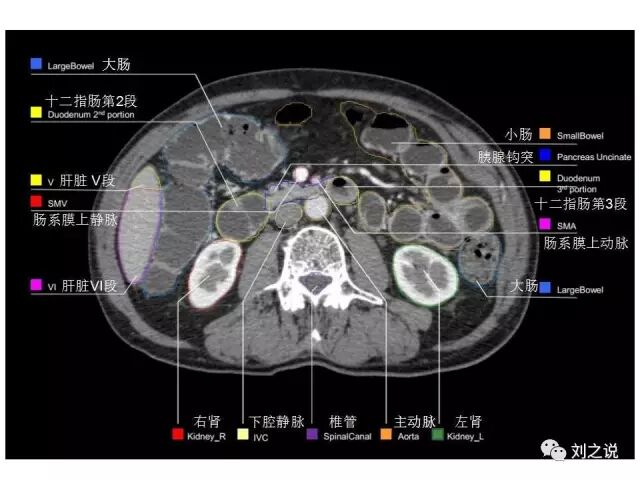

参考RTOG共识和3D-body解剖。

来源:刘之说